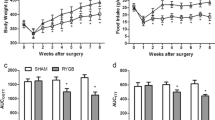

As shown in Fig. 1, there were no significant between-group preoperative differences in body weight, food intake, OGTT, and ITT. In the sham and RYGB groups, body weight reached its lowest value at 1 week postoperatively and was nearly restored to the preoperative values at 2 weeks postoperatively, while the body weight increase in the RYGB group was blunted from week 2 postoperatively. The postoperative body weights in the RYGB group were significantly lower than those in the sham group at week 4 (Fig. 1a). Daily food intake in the RYGB group was significantly decreased postoperatively between weeks 1 and 8 compared with that in the sham group (Fig. 1b).

Body weight, food intake, AUCOGTT, and AUCITT. a Body weight of the rats before and after surgery. The RYGB group showed significant weight loss compared with the sham group from postoperative week 4. b Food intake of the rats before and after surgery. Food intake of the RYGB group was significantly decreased compared with that of the sham group from postoperative week 1. c No difference in the preoperative AUCOGTT values was observed between the sham and RYGB groups. However, the AUCOGTT values were significantly reduced in the RYGB group compared with the sham group at postoperative weeks 2 and 8. d There was no significant preoperative difference in AUCITT between the sham and RYGB groups. However, the AUCITT values for the rats in the RYGB group were decreased at postoperative weeks 2 and 8 compared with the sham group. Asterisk indicates P < 0.05 vs. the sham group

The rats in the RYGB group showed significant improvements in glucose tolerance at postoperative weeks 2 and 8, as demonstrated by the lower values of AUCOGTT (Fig. 1c). Compared with the sham group, the RYGB group demonstrated lower postoperative values of AUCITT at weeks 2 and 8, indicating improved systemic insulin sensitivity (Fig. 1d).

As shown in Fig. 2a, the fasting total bile acids were similar between the sham and RYGB groups before the operation. However, the RYGB group demonstrated significantly higher levels of fasting total bile acids than the sham group at both 2 and 8 weeks after the operation. There were no preoperative differences in the fasting serum TC, TG, and FFAs concentrations between the sham and RYGB groups. The fasting serum level of TC decreased slightly in the RYGB group at postoperative weeks 2 and 8, but there was no significant difference between the sham and RYGB groups (Fig. 2b). At postoperative weeks 2 and 8, the rats in the RYGB group showed significantly lower fasting serum levels of TG and FFAs than those in the sham group (Fig. 2c, d).

Serum total bile acids level (a) and lipid profiles (b, c, d) before and after operation. a Serum total bile acids level was significantly increased in the RYGB group compared with the sham group at postoperative weeks 2 and 8. b Serum level of TC decreased slightly in the RYGB groups postoperatively, but there was no significant difference between the sham and RYGB groups. c Serum level of TG was lower in the RYGB group than in the sham group at both 2 and 8 weeks postoperatively. d Serum level of FFAs was lower in the RYGB group than in the sham group at both 2 and 8 weeks postoperatively. TC total cholesterol; TG triglycerides; FFAs free fatty acids. Asterisk indicates P < 0.05 vs. the sham group